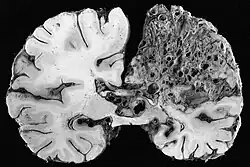

Neuropathology

Neuropathology is the study of disease of nervous system tissue, usually in the form of either surgical biopsies or sometimes whole brains in the case of autopsy. Neuropathology is a subspecialty of anatomic pathology, neurology, and neurosurgery. In many English-speaking countries, neuropathology is considered a subfield of anatomical pathology. A physician who specializes in neuropathology, usually by completing a fellowship after a residency in anatomical or general pathology, is called a neuropathologist. In day-to-day clinical practice, a neuropathologist generates diagnoses for patients. If a disease of the nervous system is suspected, and the diagnosis cannot be made by less invasive methods, a biopsy of nervous tissue is taken from the brain or spinal cord to aid in diagnosis. Biopsy is usually requested after a mass is detected by medical imaging. With autopsies, the principal work of the neuropathologist is to help in the post-mortem diagnosis of various conditions that affect the central nervous system. Biopsies can also consist of the skin. Epidermal nerve fiber density testing (ENFD) is a more recently developed neuropathology test in which a punch skin biopsy is taken to identify small fiber neuropathies by analyzing the nerve fibers of the skin. This test is becoming available in select labs as well as many universities; it replaces the traditional nerve biopsy test as less invasive.